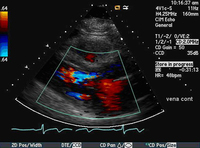

Parasternal long-axis view showing vena contracta of the aortic regurgitation jet

From the collections of Dr Sanjeev Wasson and Dr Nishant Kalra; used with permission